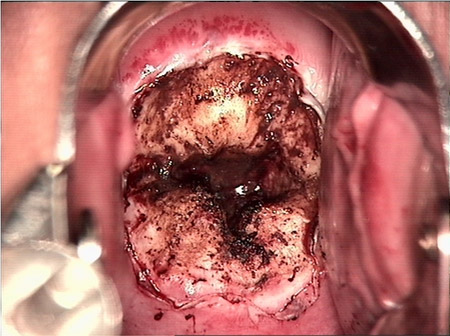

婦科leep錐切手術 CIN2-3

• CIN 2-3CIN 2-3